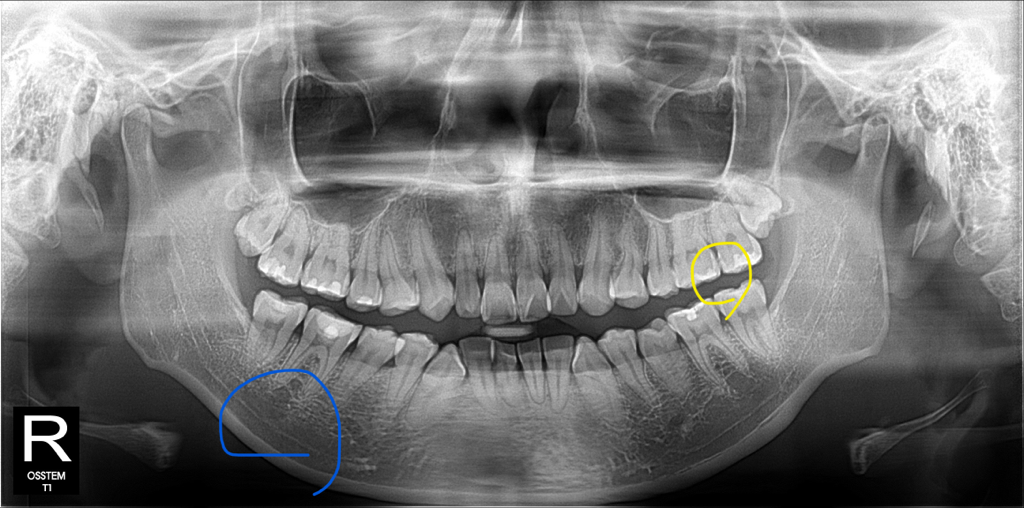

1. 파란색 동그라미친 이빨 밑에 염증이 심한건가요?

-엑스레이 사진상으로 뭔가 있어 보이지만 증상이 없다면 치료를 안하셔도 될것같습니다.

2. 노란색 동그라미친 이빨 인접면 충치는 치료를 해야될까요? 굳이 치료를 안해도되는 정도의 치료인가요?

-치아 사이가 약간 충치가 있어 보입니다. 음식물이 많이 끼시거나 불편하시다면 치료를 하시는게 좋을것같습니다.

염증이 아니라 신경관 같습니다.

인접면충치는 파노라마만 가지고 진단을 내리지 않습니다. 해당부위만 찍은 사진이 필요합니다